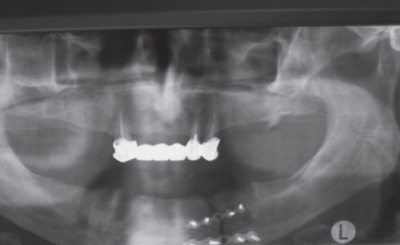

Также применялось рентгенологическое обследование нижней челюсти в прямой и боковой проекциях (рис. 1).

Рис. 1. Больная И., 68 лет. Рентгенограмма нижней челюсти у больного с переломом нижней челюсти: а – прямая проекция, б – боковая проекция